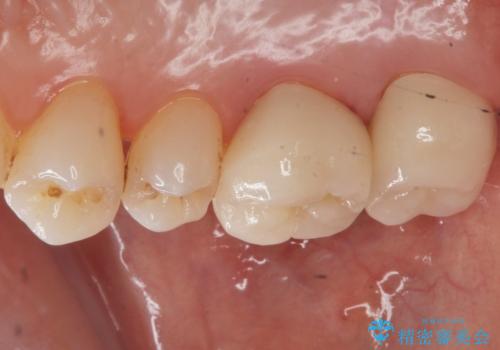

銀歯を白くしたい セラミッククラウンでの治療

銀の詰め物を除去した後、その奥にある古い詰め物も除去し完全にむし歯を取り切ったことを確認してからセラミッククラウンを装着していきます。

- 右上67 仮歯+ジルコニアクラウン:11,000+110,000円 右上7/根管治療:保険 ファイバーコア:22,000円費用は治療当時の料金となります